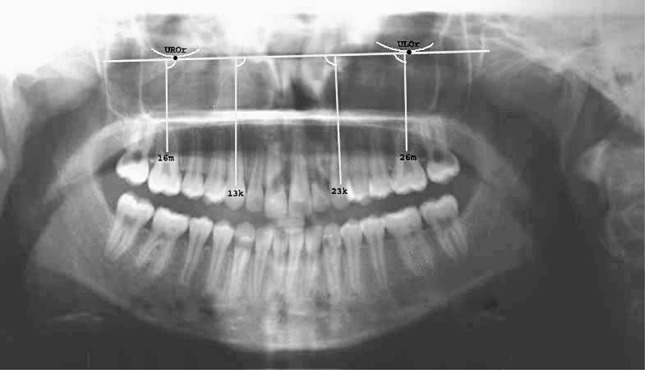

Eight patients (6 females and 2 males) who were advised for fixed orthodontic mechanotherapy with first premolars extraction in maxillary arch and/or both the arches were selected. Sixteen canine distractions (8 on the right side and 8 on the left side) were carried out with a custom made tooth-borne intra oral distraction device. Patients in age group of 14–30 years with moderate to severe crowding, increased overjet or cases with bimaxillary dental protrusion were included in the study and patients with debilitating systemic illness were excluded from the study. Cephalometric and model analysis was done and the maxillary sinus floor was traced (Fig. 1) to assess the proximity of the sinus floor with the canine root apex and surgical planning. It was planned to carry out retraction of canine by periodontal ligament distraction (PLD) on the right side and DAD on the left side under local anesthesia

Fig. 1.

Tracing of maxillary sinus

The changes that occurred during the rapid canine retraction were assessed by examining the panoramic radiographs taken before and after the distraction. All panoramic radiographs were taken with the same orthopantomograph (Orthoralix 9200, Gendex). Each patient was instructed to keep their lips in resting position. The parallelism of Frankfurt horizontal plane was affirmed. To analyze the panoramic radiographs, four reference points were determined as described by Ursi et al. [4] and two reference planes were formed by using these points (Fig. 19). Additional planes were constructed by connecting the coronal and apical points of root canals of the canines.

Fig. 19.

Reference points and lines used in the panoramic view

Apical and coronal points of the palatal root canal in the upper first molars were used in constructing the reference planes. A total of four angular measurements were made with these points and planes. The axial inclinations of the canines and molars were measured on the panoramic radiographs taken before and after the distraction.